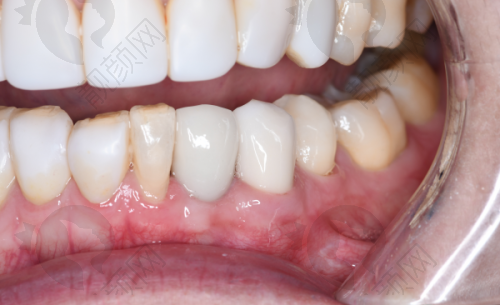

上海鼎植刘正欢种植牙实例

曾有一位患者,由于长期牙齿缺失,导致牙槽骨重度萎缩,普通的种植牙技术难以实施。刘正欢院长经过详细的检查和分析,决定为患者采用穿颧种植技术。在手术过程中,刘院长凭借不错的技艺和丰富的经验,精细操作,成功为患者植入种植体。术后,患者修复良好,牙齿功能和美观度都得到了极大的改善,对刘院长的医术赞不绝口。